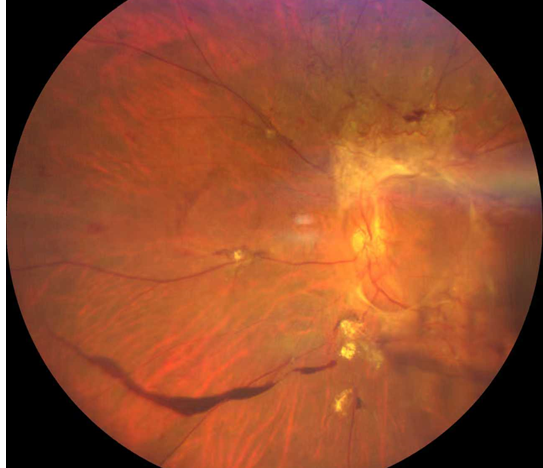

雙眼被確診為Ⅱ期增殖性糖尿病視網(wǎng)膜病變(以下簡稱“糖網(wǎng)”),并伴有黃斑水腫。

糖尿病視網(wǎng)膜病變